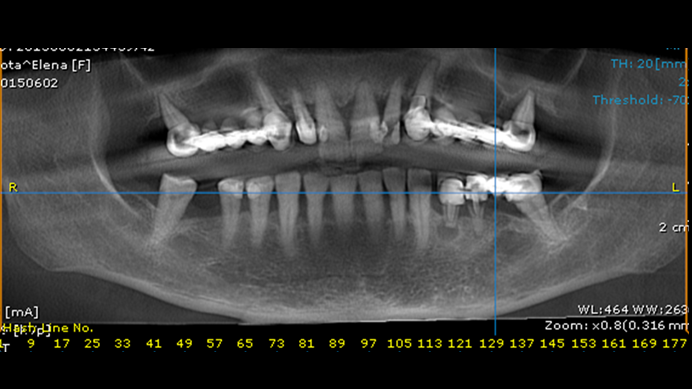

Clinical case: Extraction of all teeth in upper maxilla,

immediate implant placement, & provisionalization

- Courtesy of Dr. Iulian Filipov, Romania -

Keywords

AnyRidge, immediate placement, immediate provisionalization, maxillary fully edentulous case, initial stability, edentulous, Dr. Iulian Filipov, R2GATE, MEGA ISQ